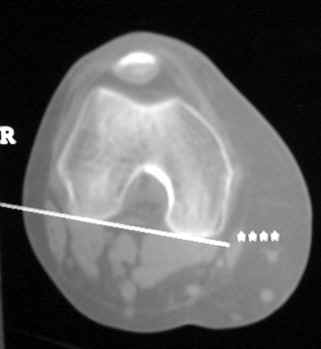

OSTEOLYSIS

CT guided biopsy